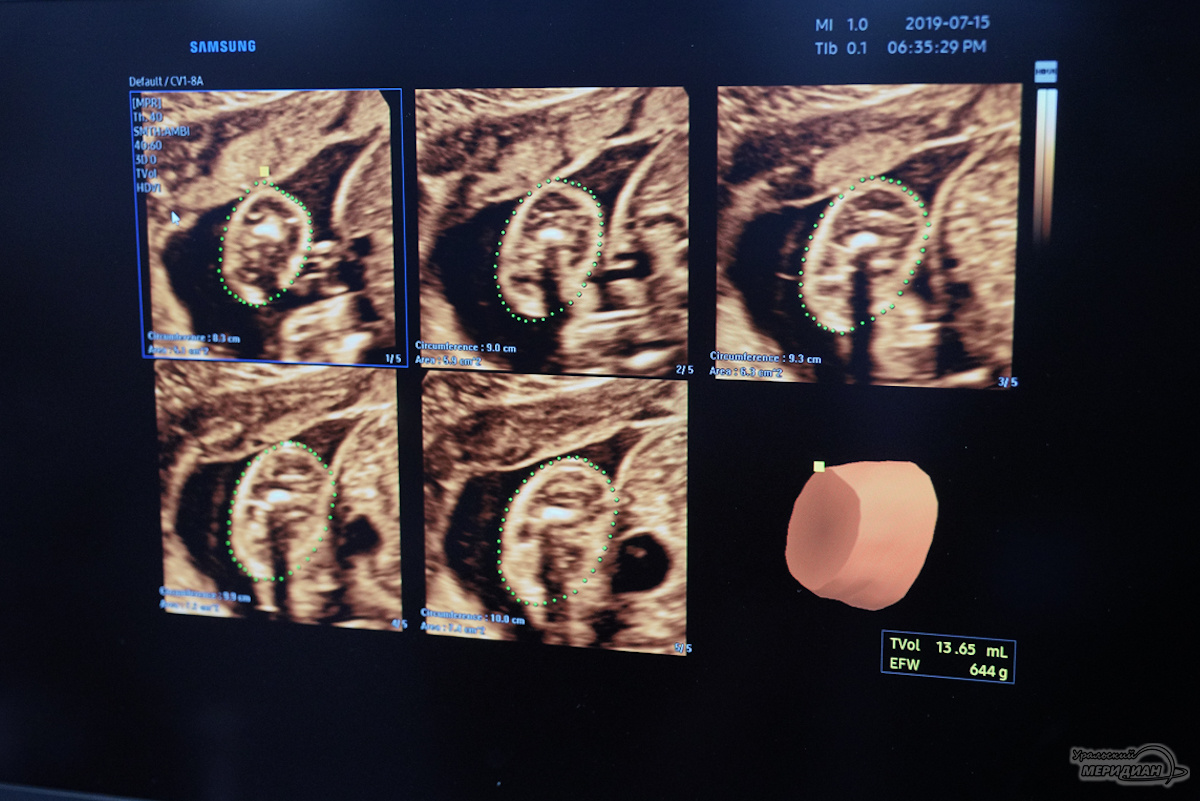

Фото: Лидия Аникина © ИА «Уральский меридиан»